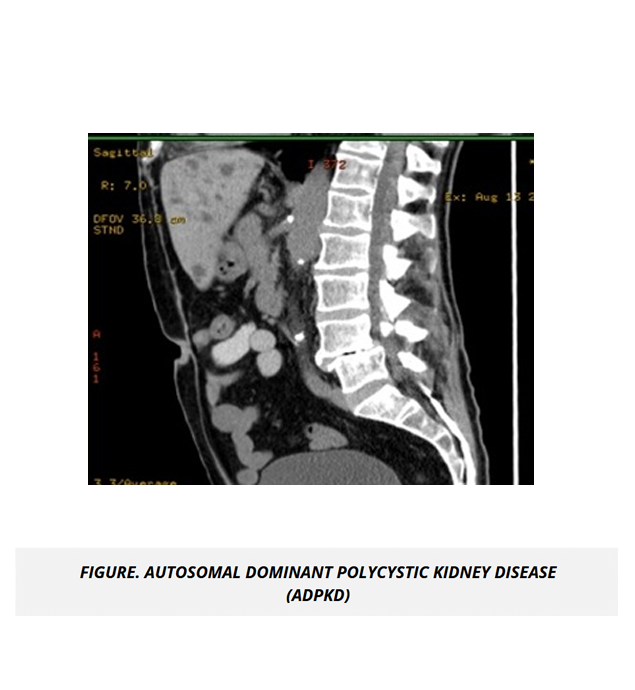

Renal and Urinary System Content Review 9% - 13%

The renal and urinary system make up questions heavily weighted on physiology-focused concepts. The UMock USMLE® Step 1 prep course provides a high-yield review of essential concepts in a clear and concise format to help you understand and apply the connection between renal tubule physiology and the diuretics that work on the tubule, as well as applying concepts in nephritic and nephrotic syndromes to clinical scenarios.

The course includes high quality radiological images and microscopic views highlighting normal and abnormal processes specific to renal and urinary diseases to give you a distinguished understanding of the application of concepts in clinical scenarios.

• Cystic Diseases of Kidney